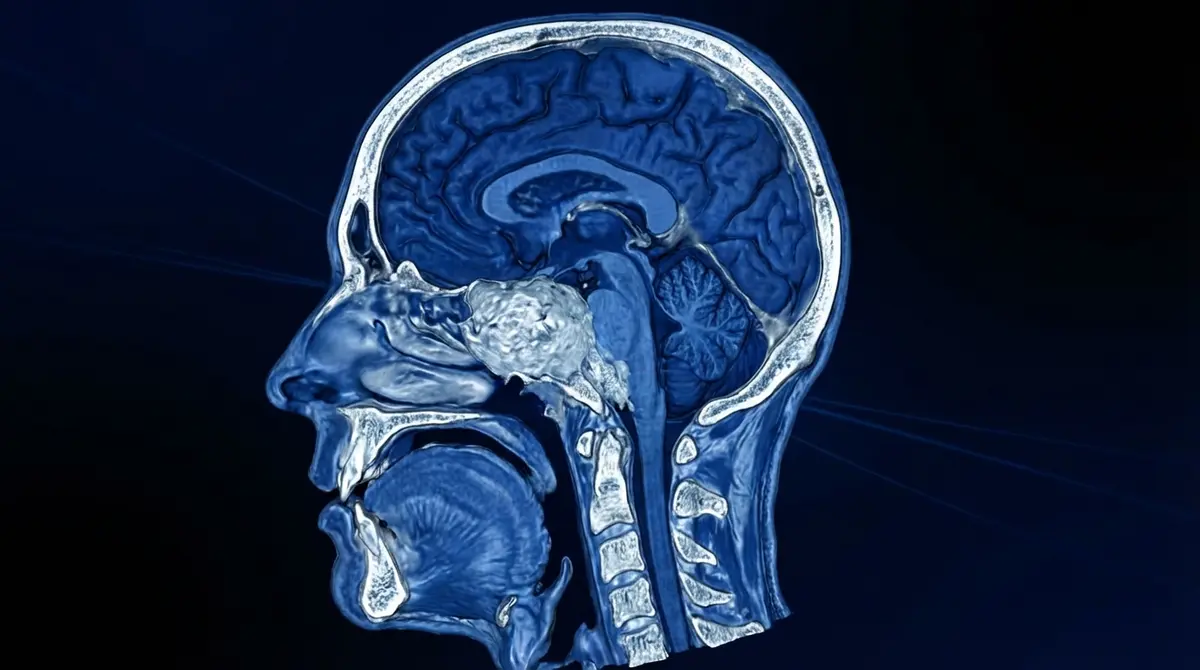

Cirurgia para remover um craniofaringioma, tumor benigno (não canceroso) que nasce na região da sela túrcica (onde fica a hipófise), frequentemente comprimindo o quiasma óptico (cruzamento dos nervos da visão) e o hipotálamo (centro de controle hormonal, fome, sede e temperatura). A via transcraniana acessa o tumor através de uma abertura no crânio.

🎯 Craniotomia Pterional Acesso pela lateral da cabeça (região temporal), permitindo visualização da base do crânio — técnica versátil para a maioria dos craniofaringiomas.

🌉 Craniotomia Subfrontal Acesso pela parte frontal inferior, útil para tumores que se projetam para frente (visualização da face inferior dos nervos ópticos).

🔬 Craniotomia Orbitozigomática Remove parte do osso orbital e zigomático para acesso mais baixo e amplo — menos retração cerebral necessária.

3️⃣ Acesso: Abertura da duramáter, retração cuidadosa do cérebro (lobo temporal ou frontal) para expor a base do crânio.

4️⃣ Dissecção: Identificação dos nervos ópticos, artérias carótidas e hipotálamo. Dissecção cuidadosa do tumor, separando-o dessas estruturas vitais.

5️⃣ Ressecção: Remoção da porção sólida do tumor e aspiração do conteúdo cístico (líquido "motor de carro").